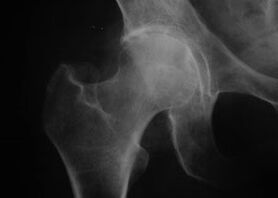

Coxathrosis, arthrosis nke nkwonkwo ukwu

Site na ọrịa a, a na-ahụ ọgwụ oyi nke arthrosis.

Ihe mgbaàmà mbụ nke coxarthrosis bụ ahụ erughị ala na nkwonkwo ụkwụ.

Na coxarthrosis coxarthrosis, ihe mgbu na-abawanye, ike isi ike na-apụta.

Ndị ọrịa nwere nnukwu ụdị coxarthrosis na-agbagha, na-ezere ịbanye na ya, ma mgbe anyị na-enwe ọfụma nke ihe mgbu ahụ dị ntakịrị.